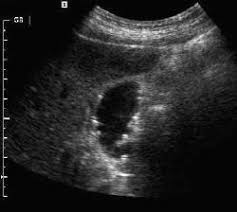

Http Liverbasics Com Echogenic Liver Html Echogenic Liver Is The Term Used To Explain Ultrasound Results Whi Ct Scan Medical Imaging Technology Liver Disease

Http Liverbasics Com Echogenic Liver Html Echogenic Liver Is The Term Used To Explain Ultrasound Results Whi Ct Scan Medical Imaging Technology Liver Disease from www.pinterest.com